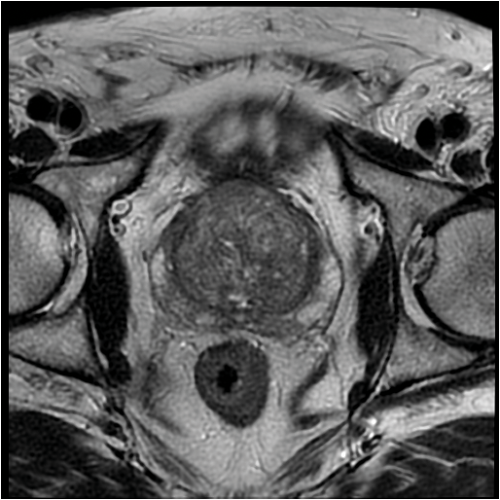

Figure 1: Axial MRI scan demonstrating BPH.